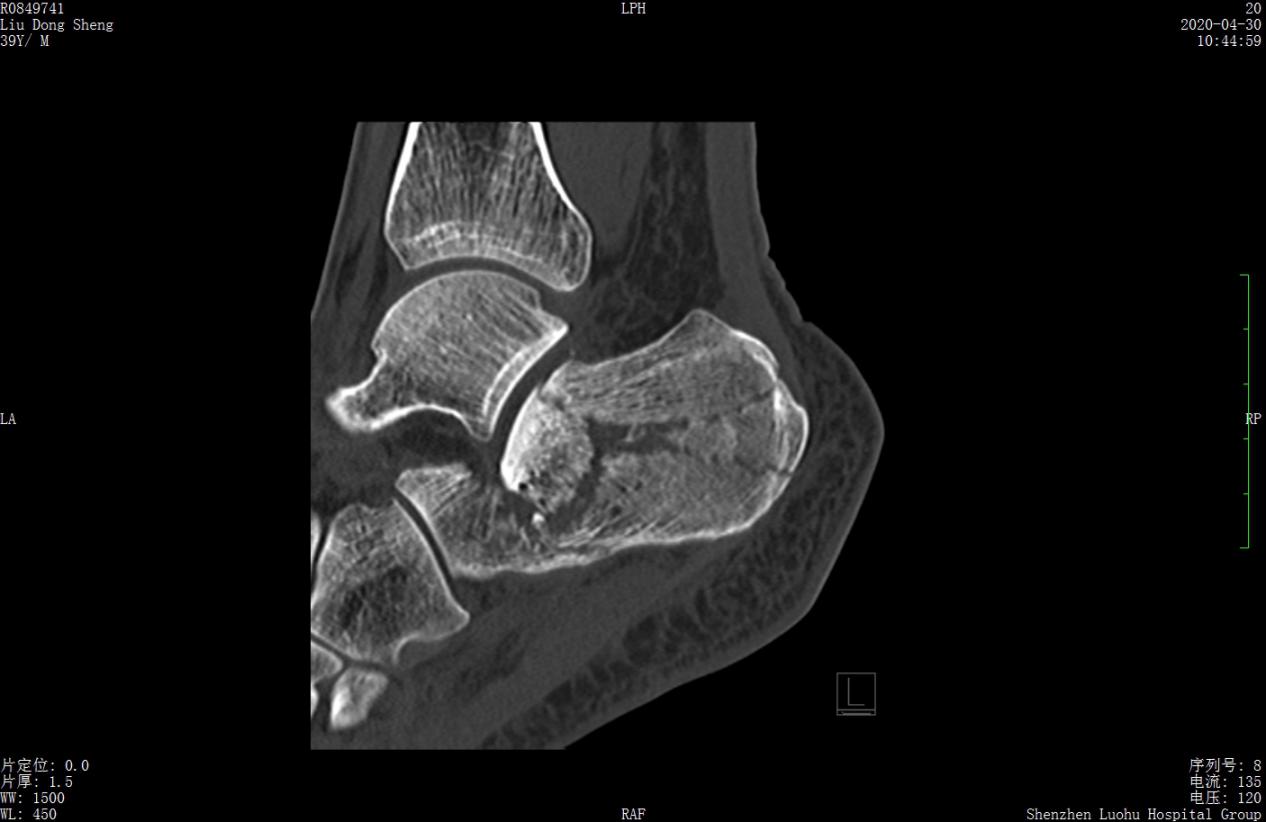

案例2影像

术前CT示跟骨粉碎骨折